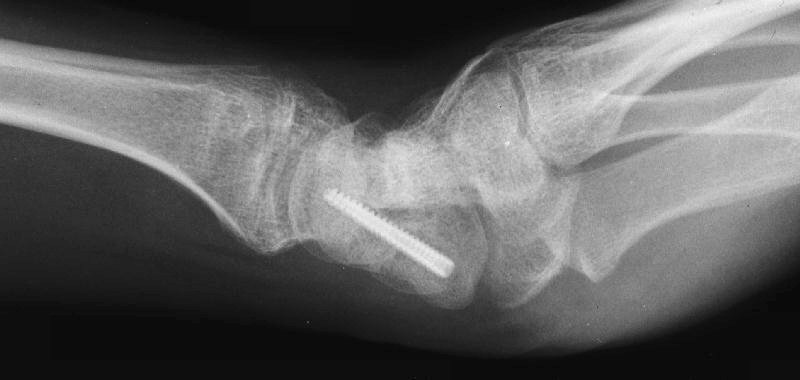

This 19 year old had been treated elsewhere with an accutrac screw for a displaced scaphoid fracture. He was noncompliant with immobilization after surgery, and developed a painful nonunion.

The nonunion was reconstructed by removing the hardware, iliac bone graft and two Herbert screws placed through new paths. Cancellous bone was packed into the old screw hole.